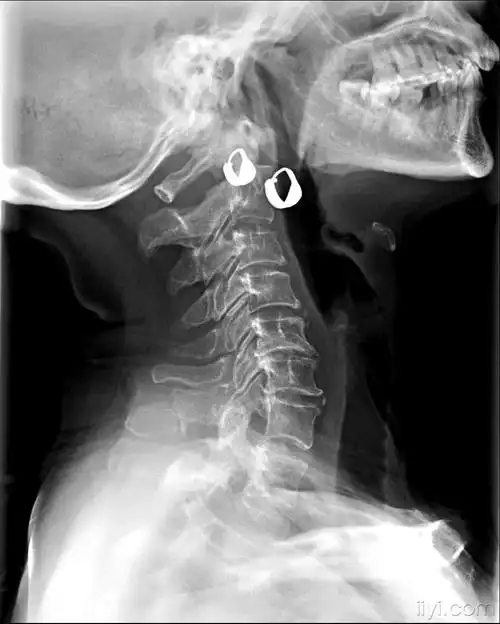

颈7棘突骨折

医疗安全 一一第7颈椎棘突撕脱性骨折